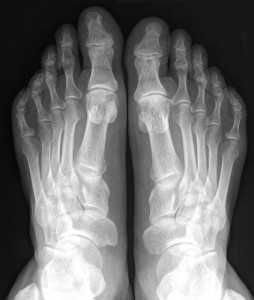

Первыми поражаются верхние и нижние конечности. Часто развивается остеопороз стопы.

Он характеризуется постоянной, слабой или средней интенсивности болью в ноге. Нередко изменяются ногтевые пластинки.

Они могут расслаиваться или становиться хрупкими, как при грибковой инфекции.

При длительном течении заболевания и отсутствии лечения возникает деформация стоп. Это затрудняет передвижение и повседневную деятельность.

Наиболее опасна остеопения шейки бедра. Это наиболее узкая часть кости, которая располагается между ее головкой и телом. При остеопорозе она часто ломается.